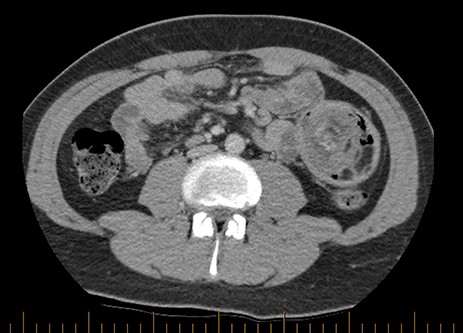

Prior to this presentation, the patient had already had an ultrasound examination and routine biochemistry performed, both unremarkable. Computed tomography (CT) imaging was performed at the time of his second presentation which demonstrated a very large intussusception in the left side of his abdomen with proximal jejuno-jejunal involvement, marked enlargement of the intussuscipiens containing the intussusceptum and an enlarged peri-gastric node measuring 17 × 14 × 14mm at the gastric cardia. There were no imaging features suggestive of ischaemic bowel or intestinal lipomatosis (see Figs 1 and 2).

Axial section of CT scan demonstrating a rim of contrast material encircling the intussusceptum, representing coating of the opposing bowel walls of the intussusceptum and intussuscipiens, also referred to as the ‘Target Sign’.